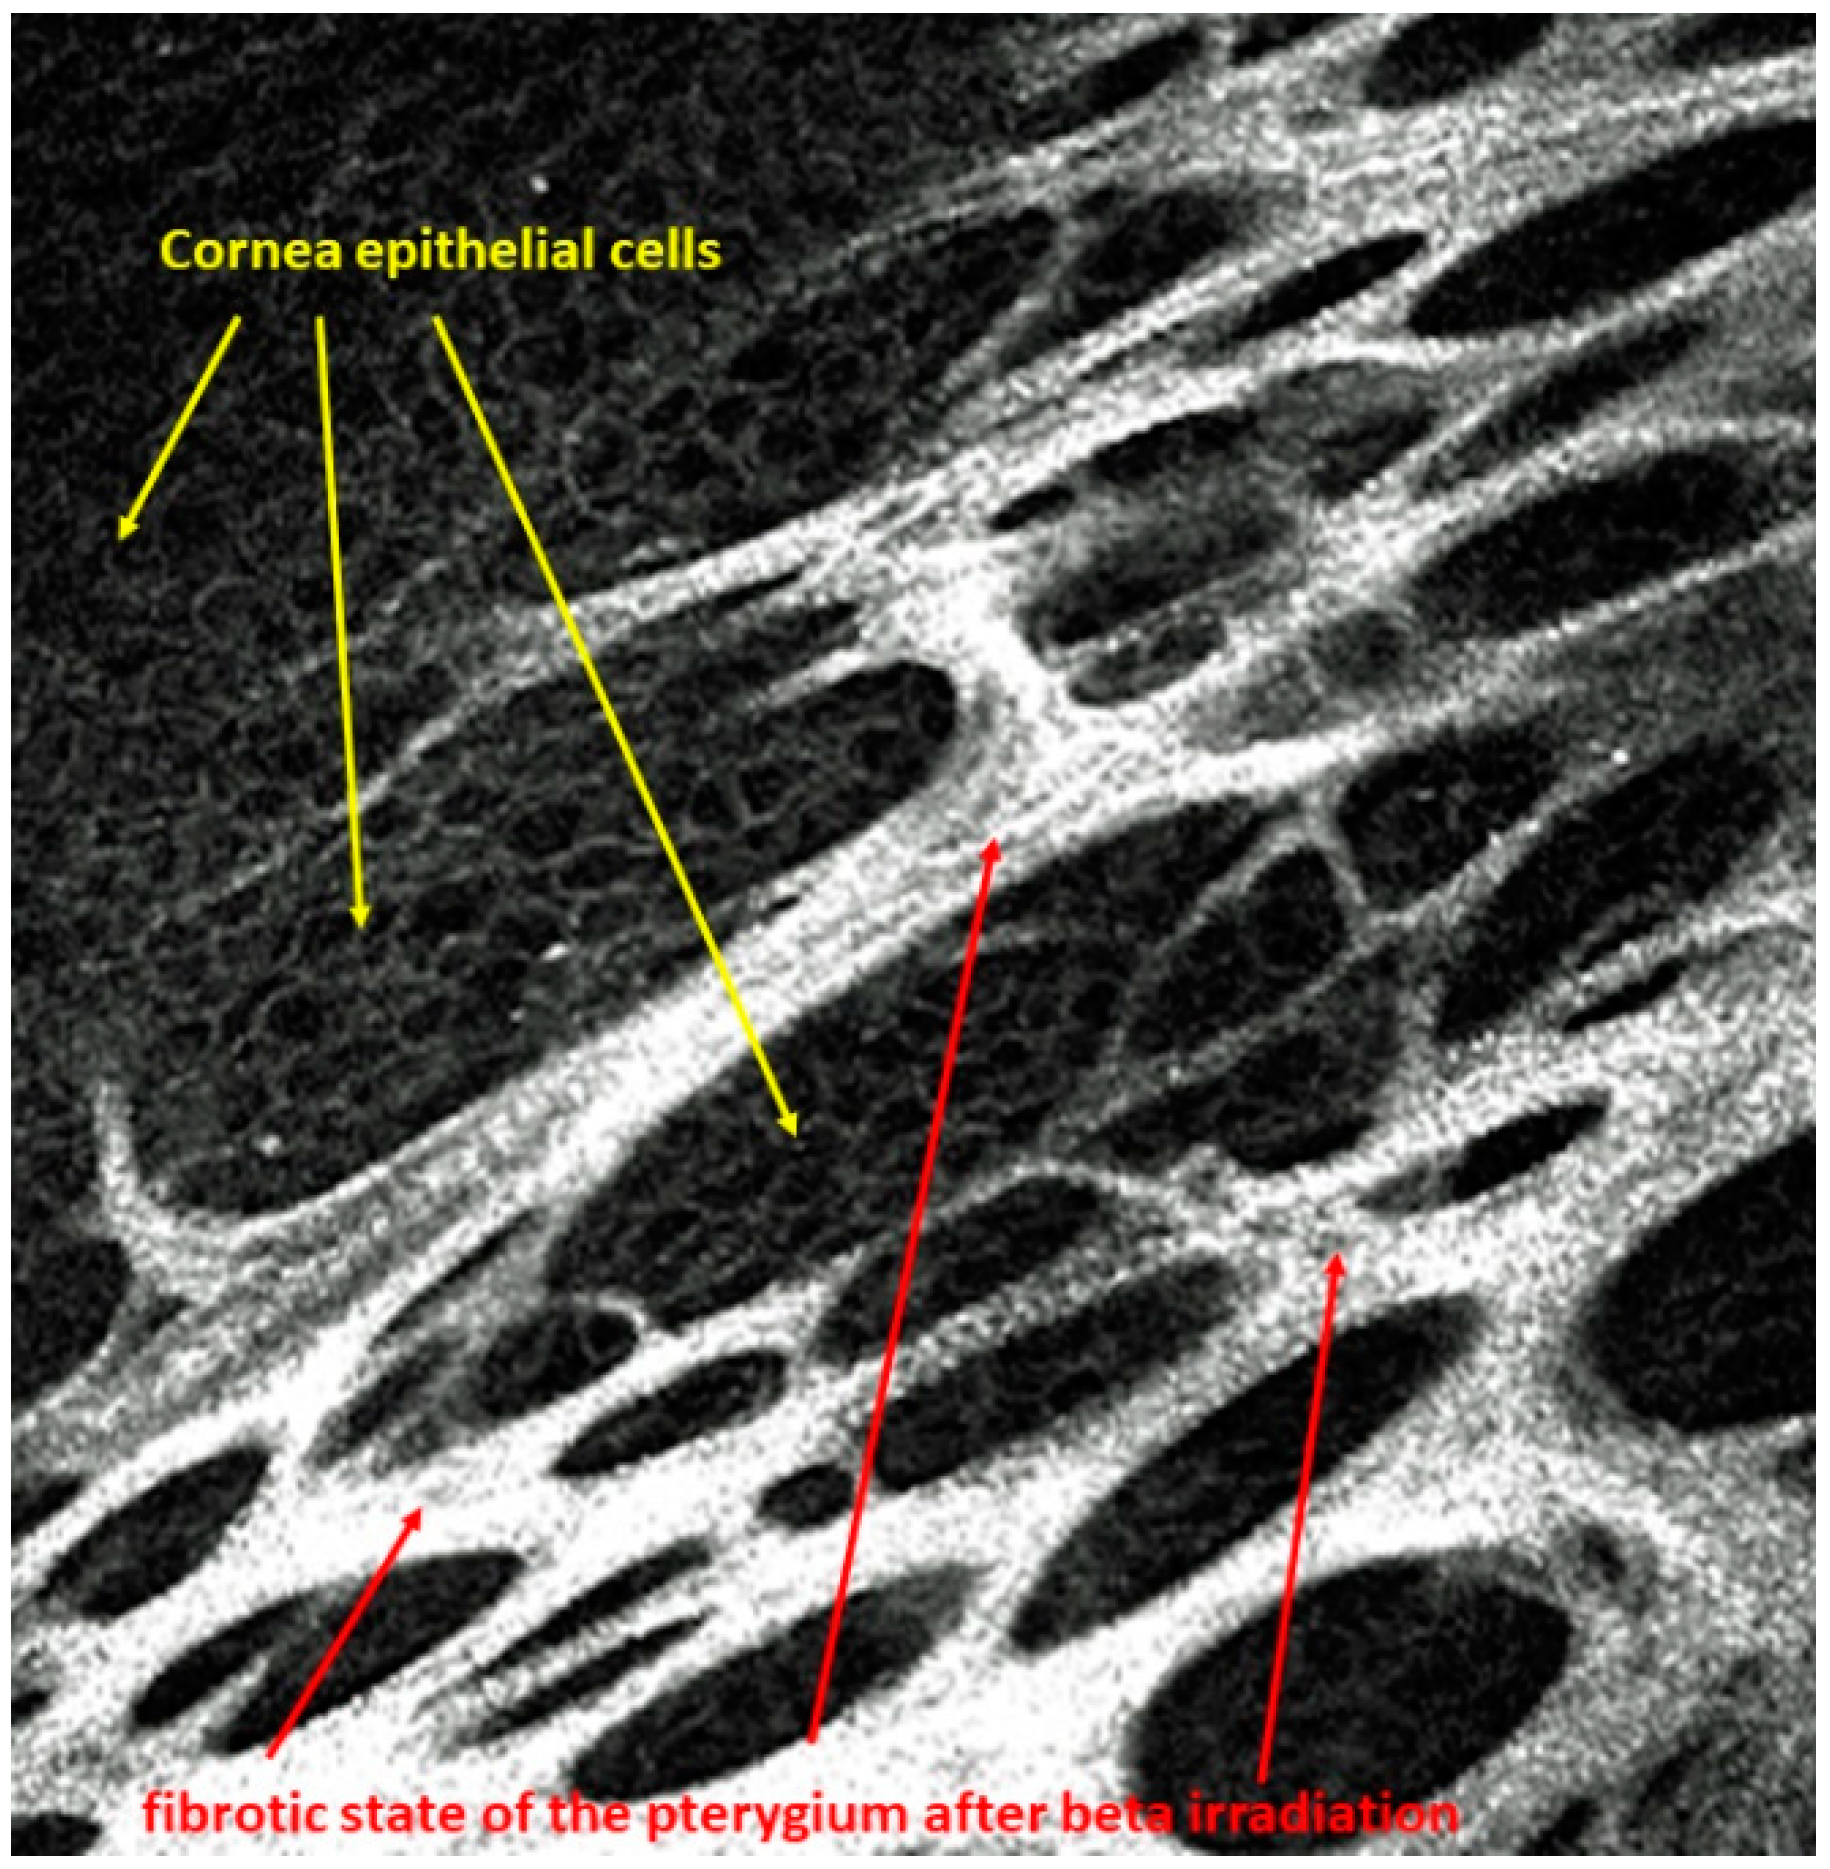

A pterygium grows proliferatively toward the center of the cornea with Bowman’s membrane as its guiding structure, which is destroyed [1,2]. A narrow zone at the head of the pterygium is vascular-free, while the base is vascular-rich. The base covers the peripheral cornea. However, the pterygium can be undermined. In particular, a confocal laser microscope can detect complete epithelial islands under the fibrous pterygium structures, as shown in Figure 1.

Figure 1.

Islets of corneal epithelial cells arranged within the fibrous structures of the pterygium after beta irradiation.